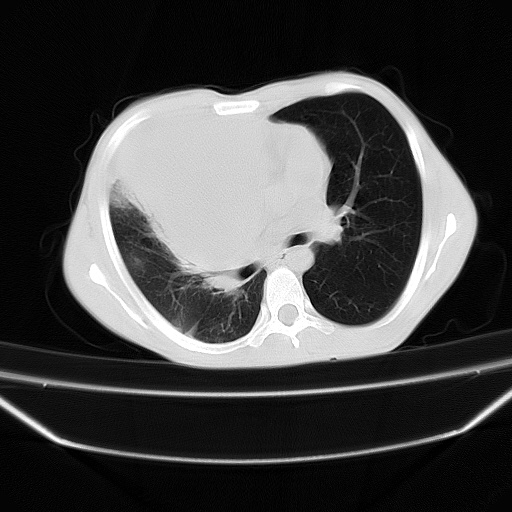

以下是引用zjzjr在2008-7-20 12:57:00的发言:[br]考虑为生殖源性肿瘤(内胚窦瘤),侵袭性胸腺瘤可能性大;右侧少量胸腔积液。

以下是引用xinliheng001在2008-7-20 21:17:00的发言:[br]右纵隔巨大分叶状软组织均质密度肿块,右上肺叶受压明显,纵隔右移、胸膜受累有少量积液和结节样增厚。应增强扫描一定会有更具诊断价值的信息。

以下是引用xinliheng001在2008-7-20 21:17:00的发言:[br]右纵隔巨大分叶状软组织均质密度肿块,右上肺叶受压明显,纵隔右移、胸膜受累有少量积液和结节样增厚。应增强扫描一定会有更具诊断价值的信息。